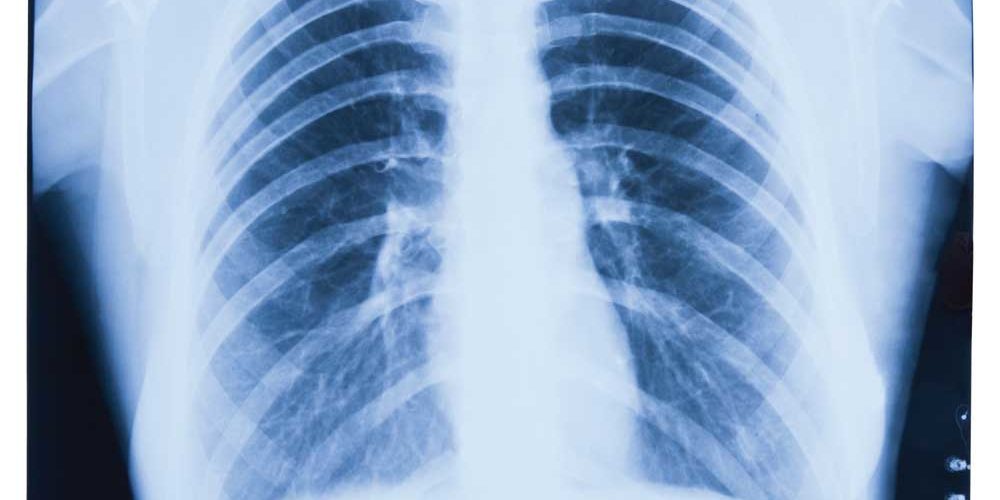

What is a lung cancer screening?

The test is a low-dose CT scan of your chest and there’s no prep needed for this screening. If your test results are negative, then it will likely be recommended that you come back annually for screening. If something is seen on your scan, it’s important not to panic. This does not mean that you have lung cancer. For example, if you have pneumonia, the finding on the CT scan may look very similar to lung cancer. It is also common for the scan to show lung nodules, which often are not cancerous. Usually, follow-up tests will be conducted to differentiate between benign and malignant conditions. “We now have a proven tool to screen for lung cancer… like mammograms for breast cancer and colonoscopy for colon cancer,” said Jay M. Barbakoff, MD, Northwell Health Pulmonary Physicians at Port Jefferson. “Early detection leads to much higher survival rates than when patients present with symptoms. ALL high-risk patients should get yearly low dose radiation CT chest screening.”